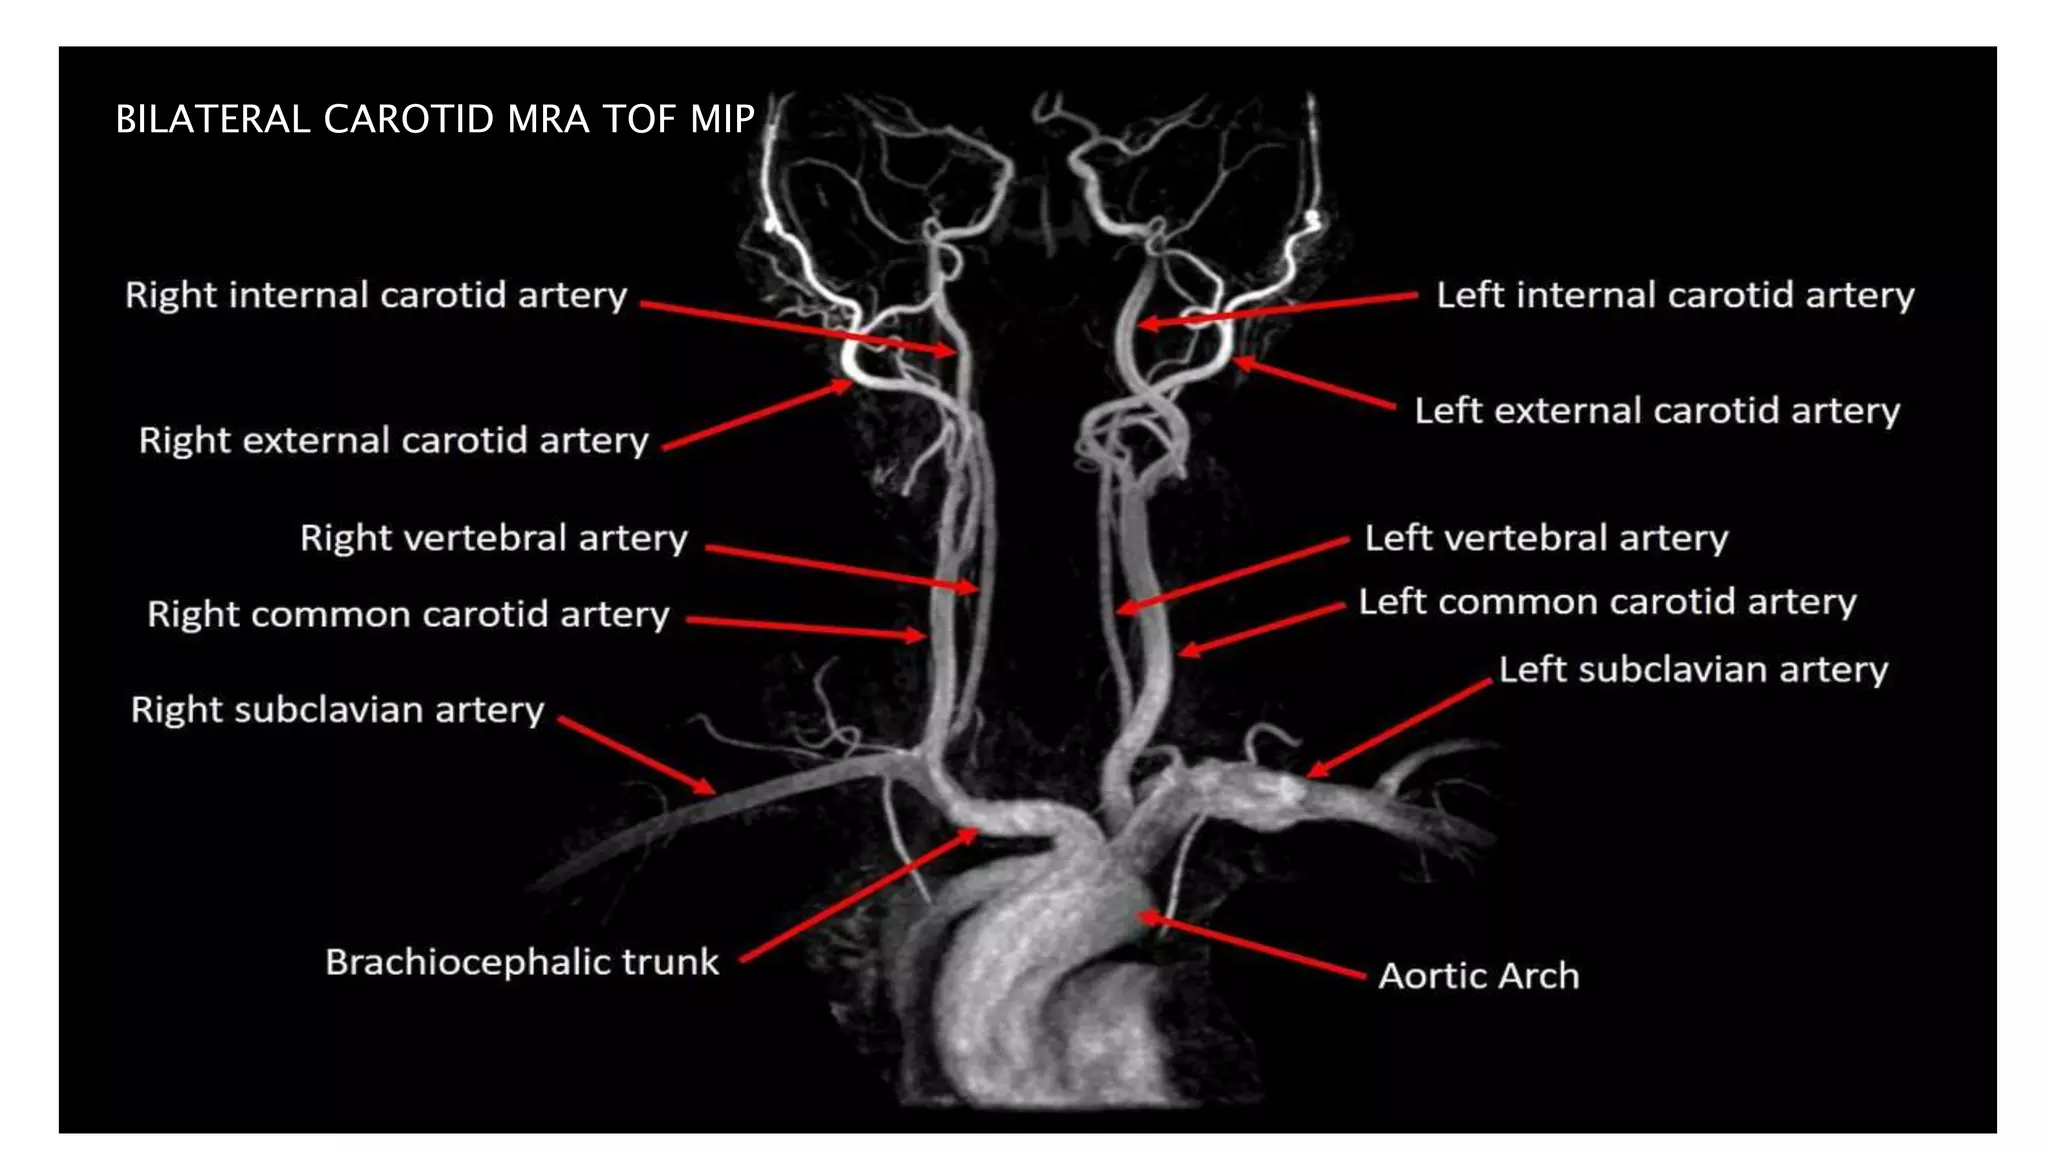

2D TOF MIP MRA 3D TOF VRT MRA

BILATERAL CAROTID MRA TOF MIP

LEFT ICA STENOSIS

• #63 Here is TOF MIP and VRT MRA showing excellent angiogram due to background suppression and better flow related signal leading to better distal small vessel visibilty

• #64 here is an example of AP VIEW of normal MR angiogram of cervicocranial arterial system

• #65 In this MR angiography of bilateral carotid system there is e/o short segment narrowing of Left ICA s/o left ICA stenosis